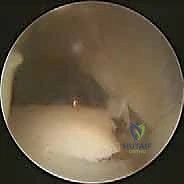

يتم عمل شق جراحي على الجانب الخارجي للكاحل. يتم عزل العصب الشظوي السطحي وحمايته بعناية فائقة. يقوم الدكتور هطيف بتنظيف المفصل من أي أنسجة متليفة، وقد يستخدم منظار الكاحل (Arthroscopy) في هذه المرحلة لمعالجة أي إصابات غضروفية داخل المفصل قبل البدء في إعادة بناء الأربطة.